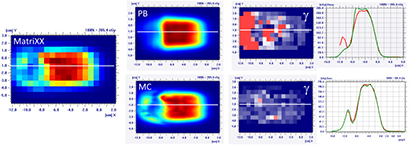

Figure 9. Dose distribution and γ analysis comparison between the MatriXX measurement and the PB or MC dose engine in a transversal plane for a lamb's head, brain target, with a gantry angle of 0° and the snout position at 30 cm. The white lines represent the dose profiles' extraction plans, the red lines are the measured data profile while the green lines represent the calculated dose distribution. The red region in the γ graph represents the area with γ > 1.

Download figure:

Standard image High-resolution imageIn the case of the more superficial target on the 'nose target' of the lamb's head, the dose differences between the PB and MC algorithm increase (figures 10 and 11 and table 4). For the gantry angle of 60°, the γ passing rate is also well below 95% in the case of small air gap (snout position at 24 cm, i.e. air gap of 1.5 cm) and the application of the splitting technique. For such a tangential entrance, the MC algorithm provides superior performances, matching significantly better with the measured data.

Standard image High-resolution imageFigure 11. Dose distribution and γ analysis comparison between the MatriXX measurement and the PB or MC dose engine in a transversal plane for the lamb's head's nose target, with a gantry angle of 60° and the snout position at 30 cm. The white lines represent the dose profiles' extraction plans, the red lines are the measured data profile while the green lines represent the calculated dose distribution. The red region in the γ graph represents the area with γ > 1.

Download figure: